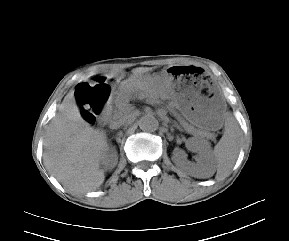

标题: CT19533:病变来源于哪?

患者,男,发现上腹部包块两月余。

病变位于肝胃间隙,实际就是位于小网膜囊(左肝下后间隙),呈轻度不均匀性强化,腹腔内及腹膜后见多发肿大淋巴结。所以我考虑肝胃间隙恶性胃肠间质瘤并淋巴结转移。

病灶强化不显著,灶周及腹膜后见多量淋巴结肿大,考虑淋巴瘤可能,其次考虑间质瘤

病灶与胰腺分界不清,来源于胰腺?